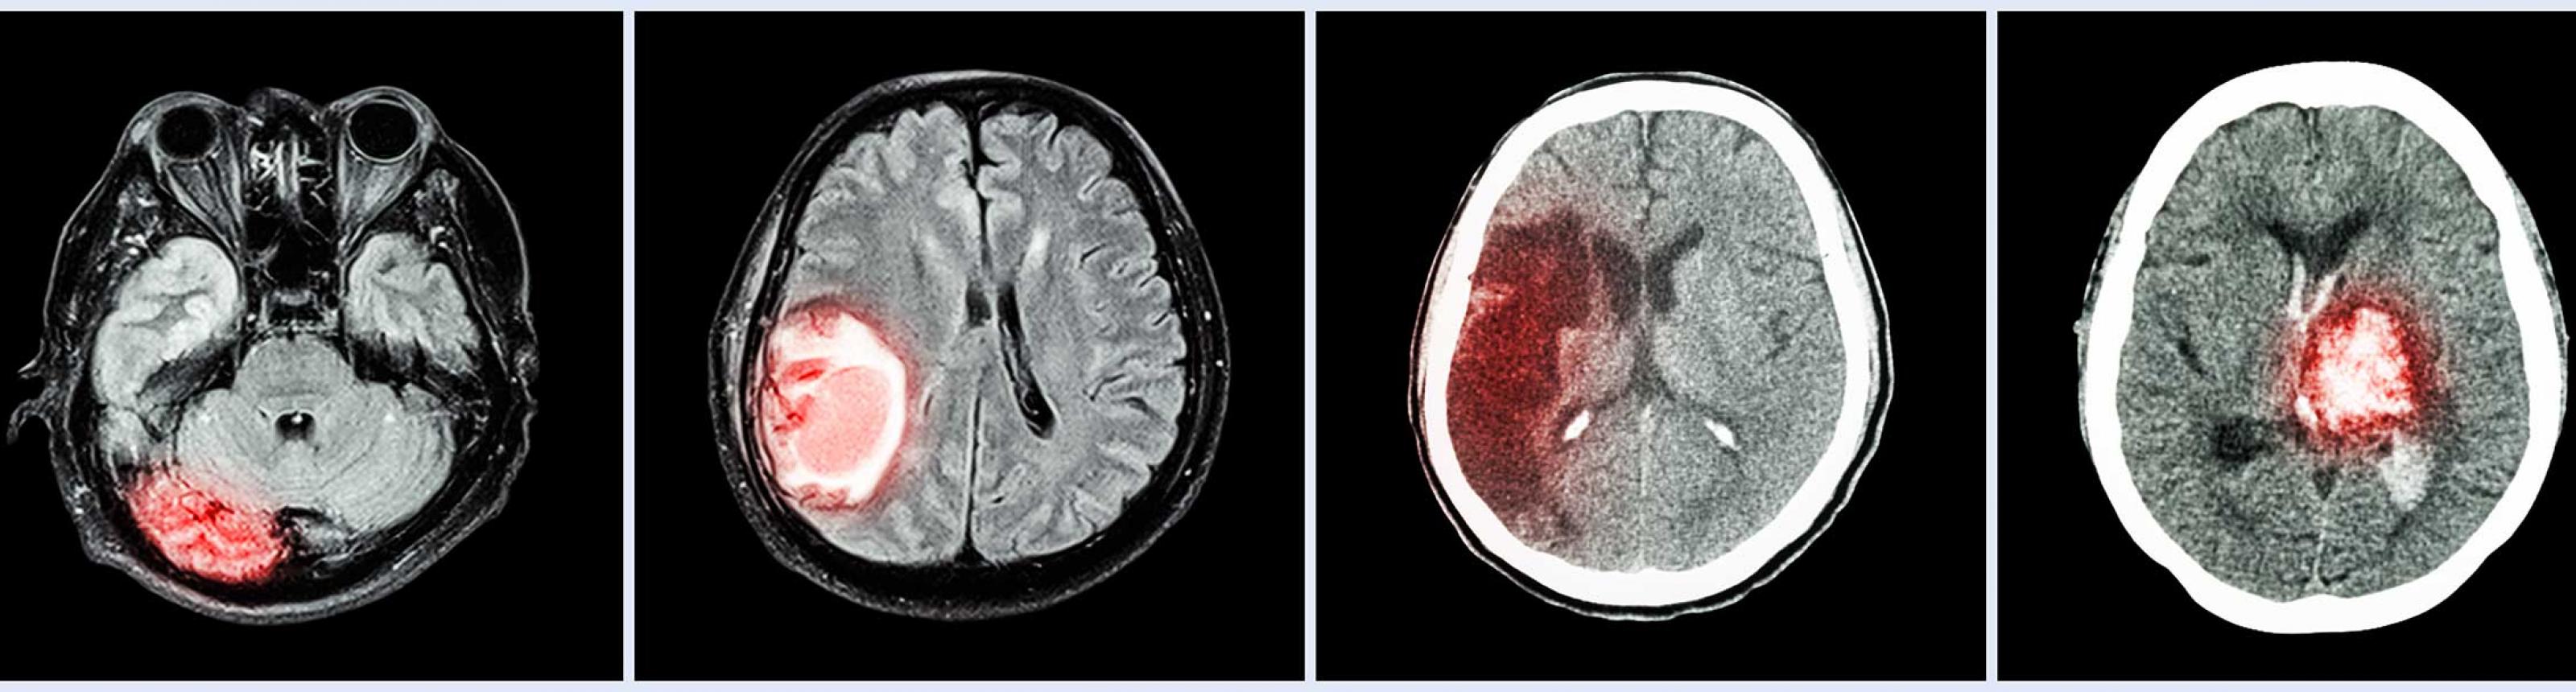

Treatments for Brain Tumors

About Treatment

At the UCSF Brain Tumor Center, we are committed to developing and providing our patients with the best possible care and most advanced therapies.

Surgery is the first-line treatment for the majority of patients with brain tumors. Our neurosurgical team has extensive experience using the most advanced techniques to treat patients across all brain tumor types.

Radiation therapy uses high-energy radiation to kill cancer cells and slow their growth. We offer a range of radiation therapies that employ different techniques to specifically target tumor tissue.

Medical therapy uses drugs to address different aspects of brain tumor growth and symptomatology. These range from chemotherapy drugs that kill cancer cells, to angiogenesis inhibitors that limit a tumor’s ability to form blood vessels and thus survive.

Our researchers are continually developing and testing new experimental diagnostics and therapies to improve patient outcomes and advance the field of brain tumor care.